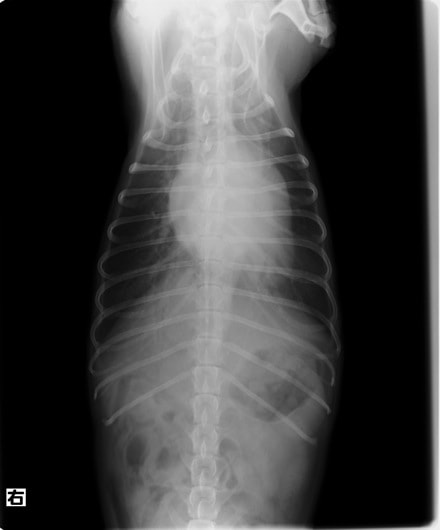

症例1:【マルチーズ 12歳齢 去勢オス】

A:胸部レントゲン写真 正面像

胸部レントゲン検査において重度の心拡大と肺水腫が認められた。超音波検査では、重度の僧帽弁閉鎖不全症、三尖弁閉鎖不全症、中程度の大動脈弁閉鎖不全症を合併していることが判明した。三尖弁逆流速度から肺高血圧症が示唆された。